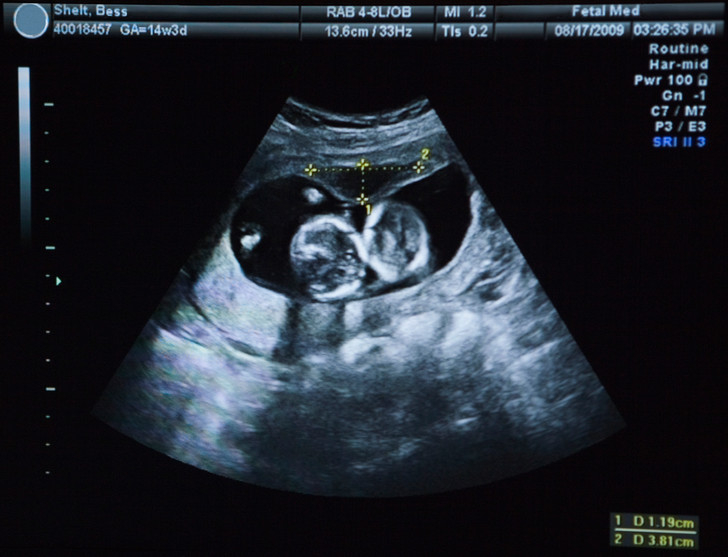

Состояние органа определяется с помощью УЗИ. Специалист изучает толщину плаценты, проверяет, не образовались ли на ней кисты и кальциевые отложения.